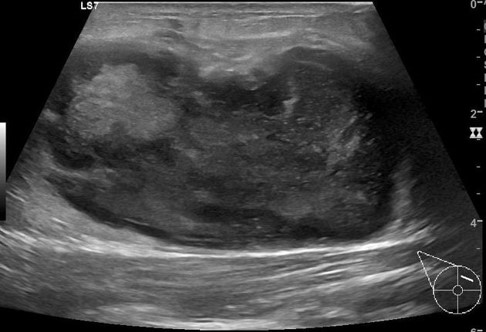

The ultrasound features of an abscess include:

-

A well-circumscribed, irregular hypoechoic to heterogenous, typically multiloculated, lesion

No internval vascularity

Posterior acoustic enhancement from fluid

Echogenic, vascular rim (or thickened wall).10,11

Image 2

Image 3

Images 2 and 3: Trop et al 2011 (12)